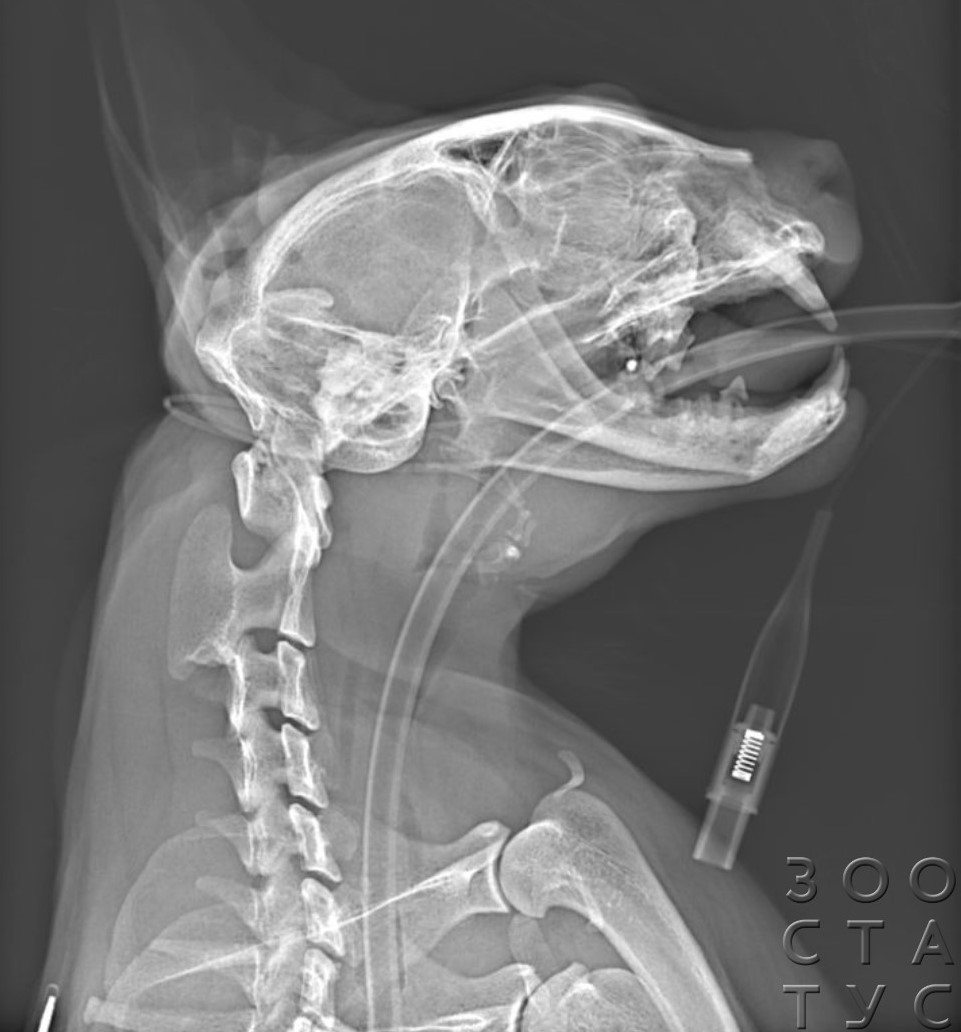

В некоторых случаях необходимо сделать несколько снимков - например, при политравмах может быть нужен и рентген головы, челюстей, рентген лап. Иногда для определения проблемы в желудочно-кишечном тракте проводят серию снимков с рентгеноконтрастным веществом. При некоторых травмах позвоночника показана миелография - введение контрастного вещества под оболочки спинного мозга.

Не стоит бояться седации - риск для животного при проведении процедуры под наблюдением врача минимален. Для кошки с возможной травмой, сильным стрессом седация менее опасна, чем жесткая фиксация, необходимая для проведения исследования. Стресс может также служить пусковым фактором для многих патологий, например, идиопатического цистита, поэтому чаще седация является более предпочтительной для проведения исследования, в отличие от собак, для кошек сама ситуация с фиксацией будет очень стрессовой вне зависимости от того, с владельцем она находится, или нет. Противопоказанием могут быть только серьезные кардиологические патологии, поэтому желательно проводить диспансеризацию своей кошки или предварительно, если необходимость сделать рентген плановая, посетить анестезиолога и кардиолога.